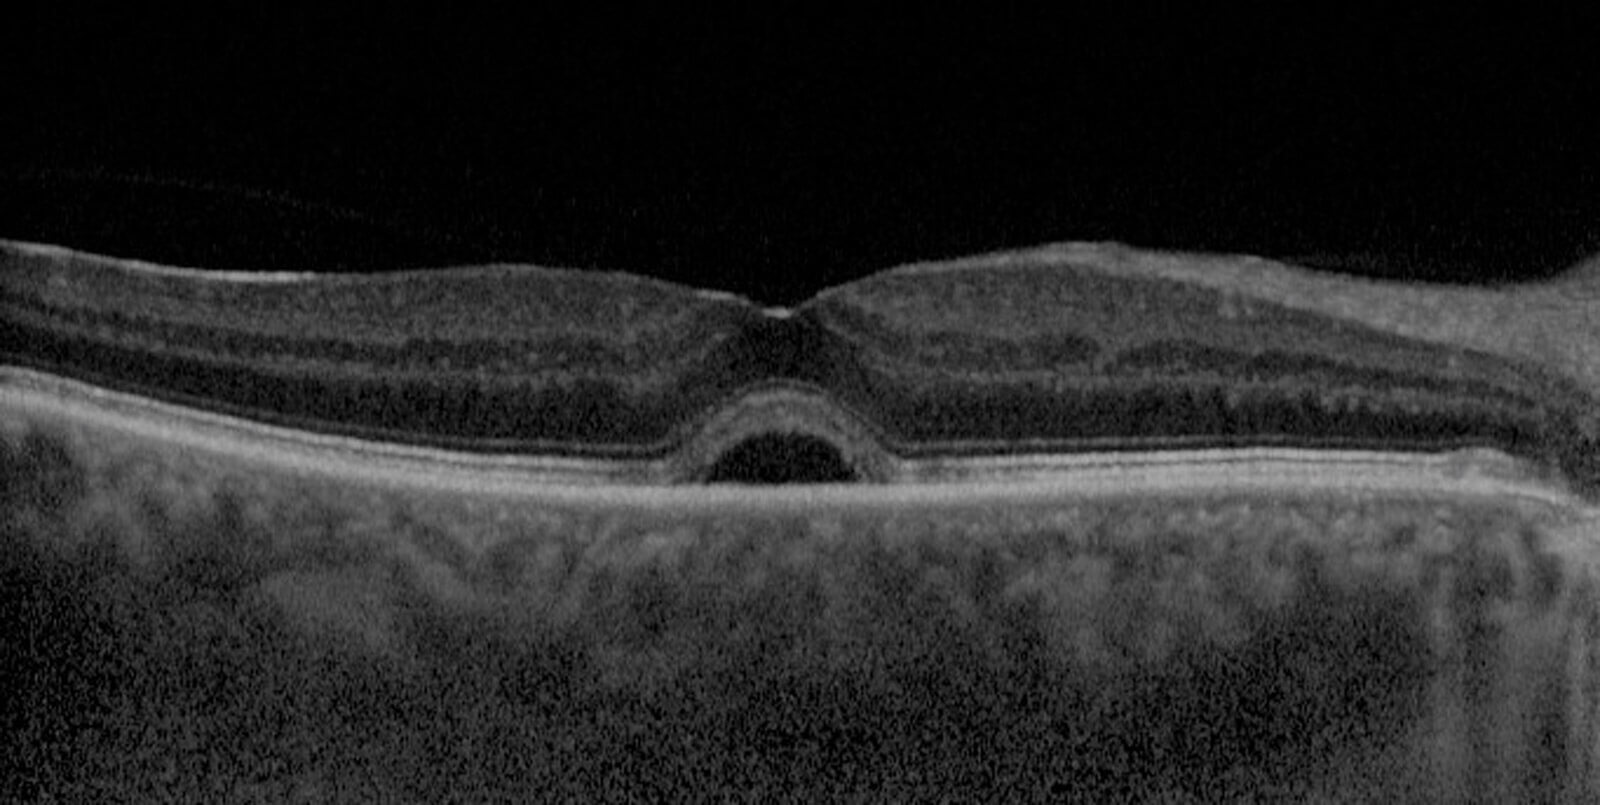

Figure 3: SD-OCT scan of subretinal fluid.

Subretinal fluid: Space of separation of the neurosensory retina from the RPE.

Retinal pigment epithelium detachment (PED): Known as retinal PED, this is the detachment between the RPE and Bruch’s membrane, which usually appears as a single hyper-reflective layer in OCT scanning. This sign can be classified as:

- Serous

- Fibrovascular

- Drusenoid.